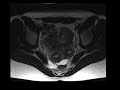

Uterine didelphys

Patient with known uterine anomaly. MR images demonstrate a double uterus with two separate cervices antwo seprate vaginas, in keeping with a uterine didelphys.